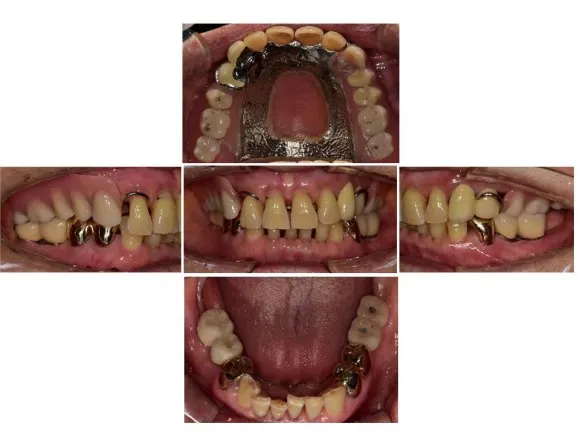

서울 큰나무 치과에 방문해 주신 70대 여성 환자의 케이스를 보겠습니다.

이 환자분의 경우, 5년 전에 위아래 모두 보험 틀니를 제작하셨지만 불편하여 잘 끼지 않는 상태셨고, 오른쪽 위에 이가 부러져 뿌리밖에 남지 않은 상태였습니다.

전후 사진으로 비교해보겠습니다.

전

후

상악(위턱)의 틀니도 수리하여 편안하게 사용할 수 있게 되었고, 하악(아래턱) 또한 네 개의 임플란트로 인해 어금니 없이 생활하시던 예전 모습에 비해 저작 기능을 회복하여 훨씬 높은 만족감을 느끼실 수 있었습니다.